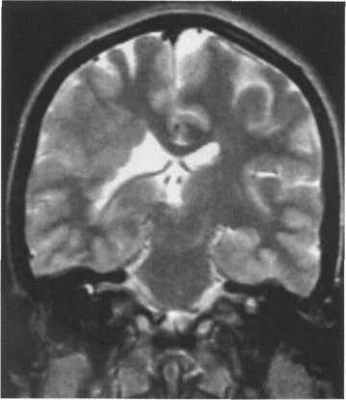

Рис. 3.19. Перивентрикулярная гетеротопия. МРТ. а - IR ИП, аксиальная плоскость; б - IR ИП, корональная плоскость.

Множественные узлы гетеротопии располагаются вдоль стенок боковых желудочков.

Перивентрикулярная узловая гетеротопия характеризуется четко очерченными узлами, расположенными вдоль стенки желудочка мозга. Узлы могут быть как одиночными, так и множественными и обычно вдаются в полость желудочка (рис. 3.19).

Перивентрикулярная и субкортикальная гетеротопия как с изменением, так и без изменения строения коры проявляется узловой перивентрикулярной гетеротопией и скоплением серого вещества в субкортикальных отделах. Поражение в большинстве случаев одностороннее. Субкортикальное скопление серого вещества может приводить к локальной деформации борозд и утолщению коры (рис. 3.20).

Рис. 3.20. Перивентрикулярно-субкортикальная гетеротопия. МРТ.

а - IR ИП, аксиальная плоскость. Узлы гетеротопии располагаются вдоль стенки левого бокового желудочка и в субкортикальных отделах белого вещества. Между субкортикальными узлами сохраняются прослойки белого вещества. Поверхность коры деформирована.

б - Т2-ВИ, корональная плоскость. Субэпендимальные узлы вдаются в полость левого бокового желудочка, что делает его контуры волнистыми.